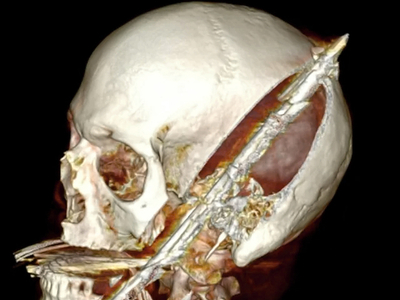

Self inflicted speargun injury to head

Ouch...poor guy...